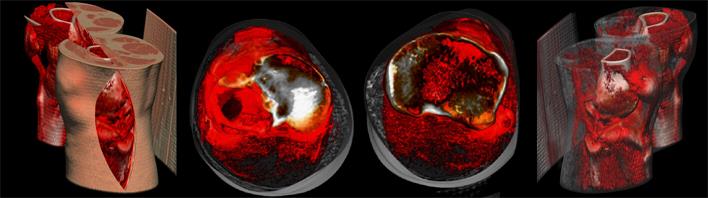

- 數(shù)字模擬內(nèi)植物選擇及放置位置

聞泰數(shù)字骨科專業(yè)軟件平臺已預(yù)設(shè)聞泰百得全部內(nèi)固定產(chǎn)品和器械,方便術(shù)前規(guī)劃和內(nèi)植入物選擇